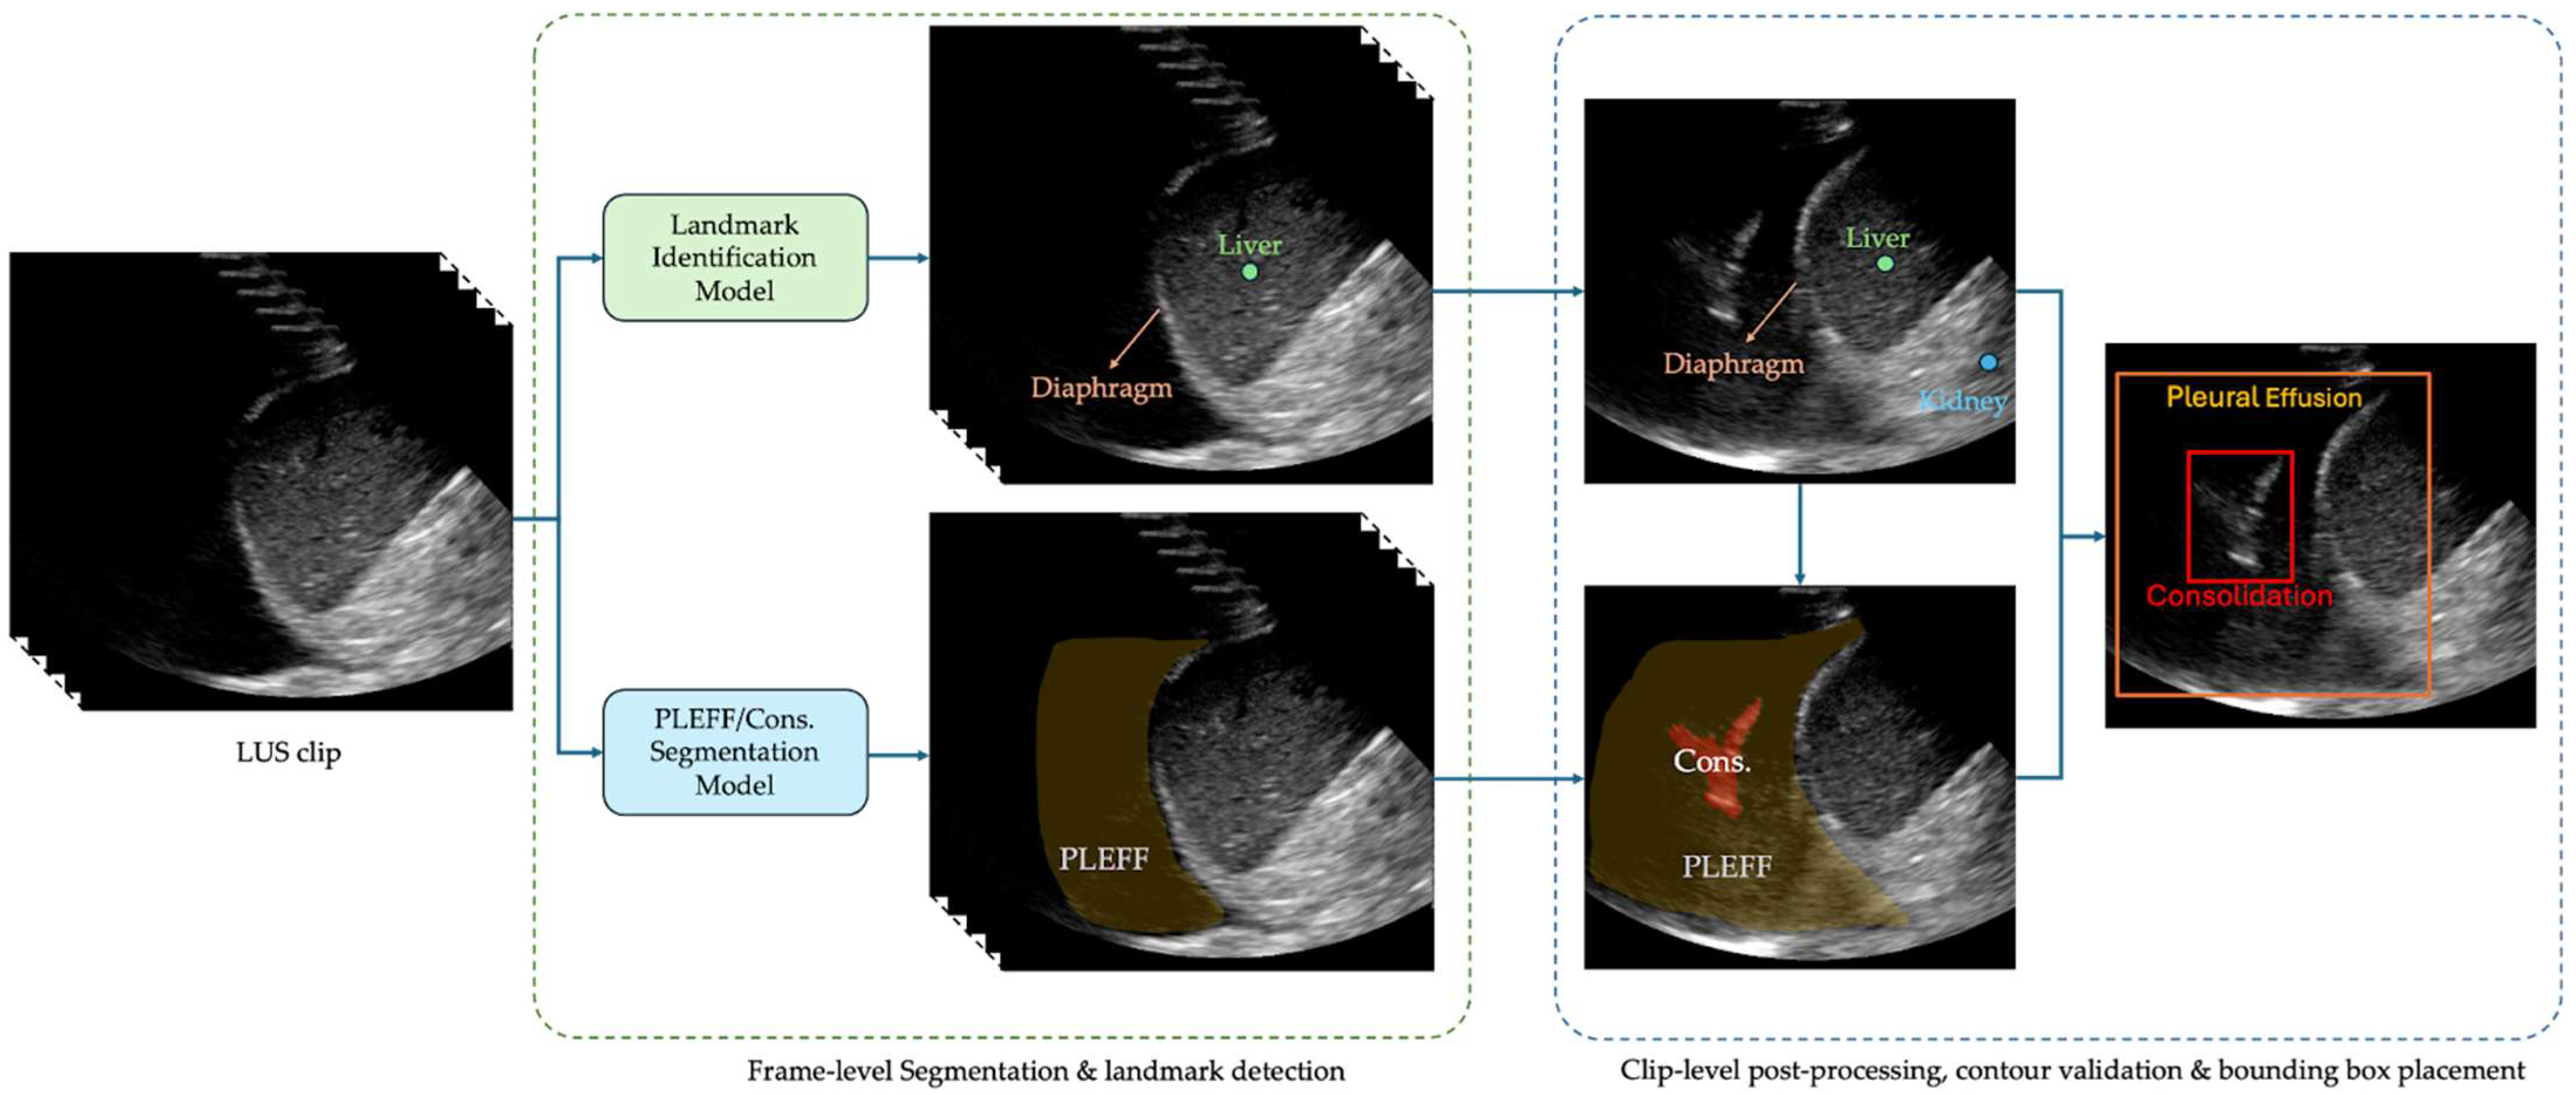

2.4. Exo Lung AI Software